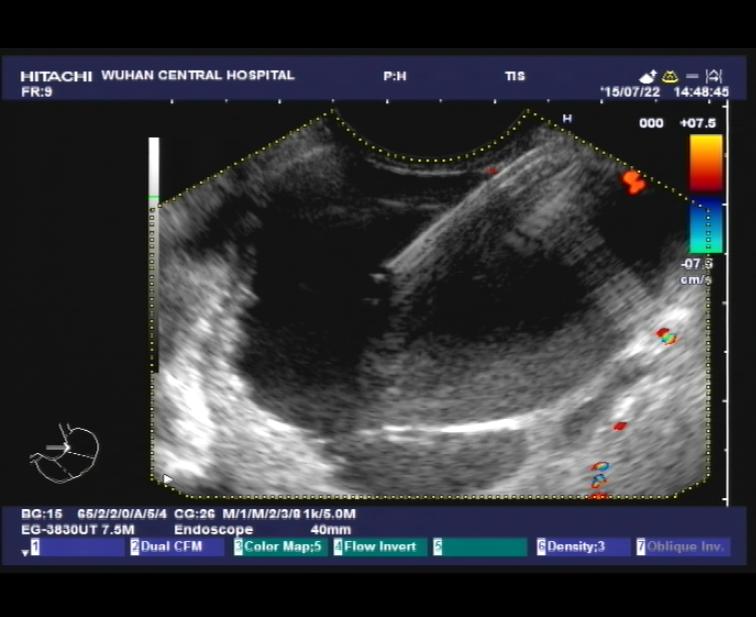

【2016年第6期】内镜超声引导下细针抽吸术治疗肝左叶囊肿的初步应用

近期我们为 3例患者成功实施了EUS引导下肝囊肿穿刺抽吸+硬化剂注射术治疗(超声主机 HITACHI EUB-5500,超声胃镜PENTAX EG-3830UT,穿刺针COOK ECHO-3-19,硬化剂:1%聚氧乙烯月桂醇醚(Lauromacrogol,聚桂醇)注射液,国产陕西天宇制药,国药准字:H20080445),现报道如下